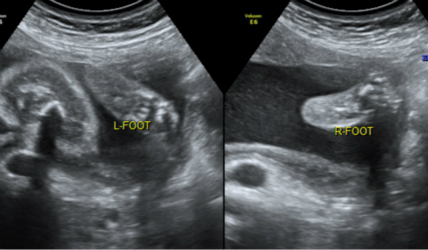

注意:虽然产前超声可以诊断大多数的胎儿结构畸形,但是超声检查仍然有它的局限性。即使用最好的设备和最优秀的超声医生仍不可能诊断全部的胎儿畸形,如胎儿手指和脚趾的畸形,耳朵形态和位置的异常,单纯的房间隔缺损或室间隔缺损等。超声不能诊断功能上的异常,如脑瘫、智力障碍、听力障碍及代谢性疾病等。甲状腺、耳、生殖系统不在检查范围内。

2.妊娠18周~24周超声检查:主要进行胎儿结构畸形的系统筛查。此时期胎儿各器官已发育成熟,系统产前超声检查可记录胎儿各器官结构包括头颅、面部、胸腹腔、心脏、肝脏、双肾、肢体及胎盘等结构,可发现大多数胎儿结构畸形。此阶段是观察胎儿结构和诊断胎儿畸形黄金时段,我们建议所有孕妇在此阶段务必接受一次超声检查。